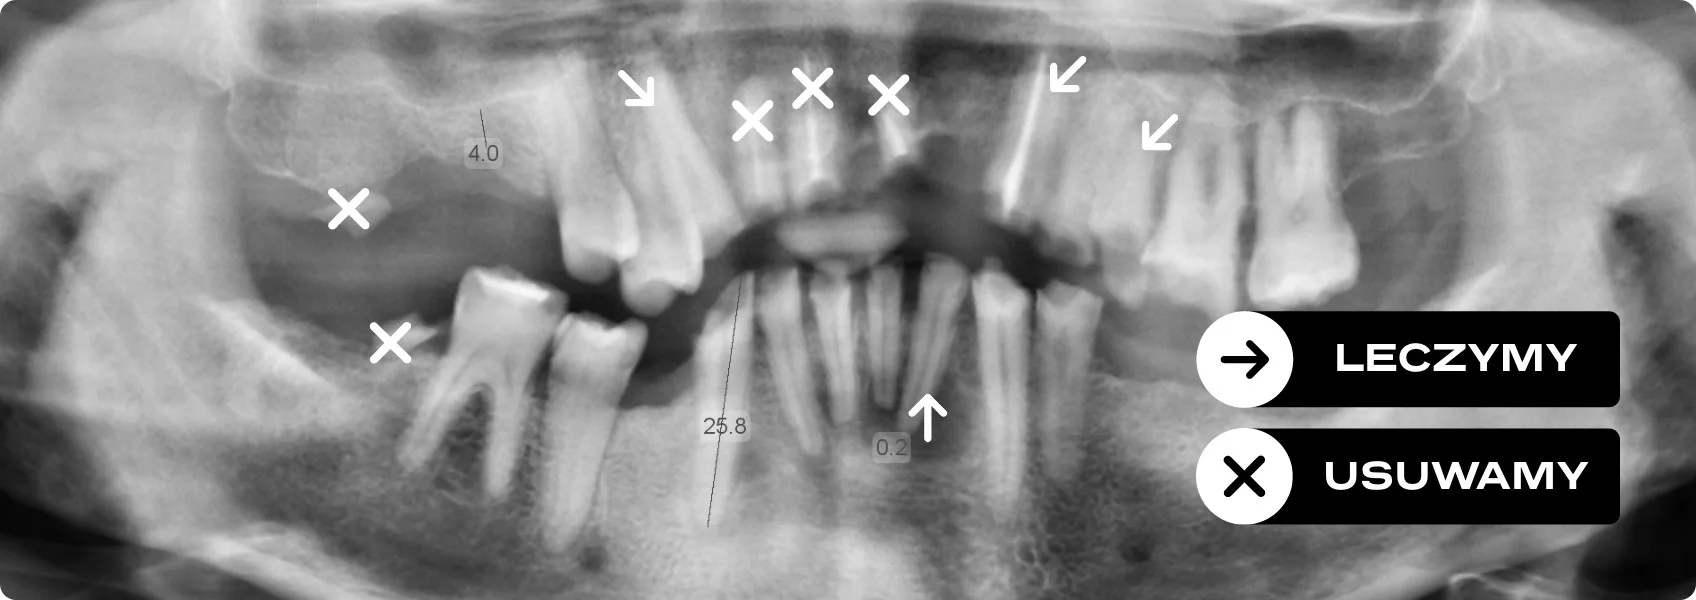

Doktor Ewa i nasza specjalistka od endodoncji, lek. dent. Katarzynie Morozik, przeanalizowały zdjęcia RTG Pacjenta. Na ich podstawie oceniły, które z chorych zębów mają szansę na ratunek dzięki leczeniu kanałowemu.

Zanim mogliśmy pomyśleć o pięknej odbudowie, musieliśmy stworzyć idealnie zdrowe środowisko w jamie ustnej. Tylko w ten sposób minimalizujemy ryzyko powikłań i awarii.

Doktor Katarzyna przeprowadziła pod mikroskopem skomplikowane leczenie kanałowe, wzmacniając te zęby, które rokowały nadzieję.

Następnie jama ustna Pacjenta przeszła pełną sanację, czyli kompleksowe działania lecznicze. Co to oznacza w praktyce? Pozbyliśmy się wszystkich ognisk infekcji, usunęliśmy zęby, których nie dało się już uratować, i dokładnie oczyściliśmy pozostałe. Ekstrakcjami zajął się nasz chirurg szczękowo-twarzowy, dr n. med. Piotr Chomik.

Dopiero na tak przygotowanym, zdrowym „placu budowy” mogliśmy zaplanować stabilną i bezpieczną rekonstrukcję protetyczną.